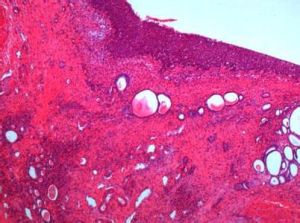

圍有水腫充血和結核結節,其後會逐漸蔓延到三角區和對側輸尿管口,甚至到全膀胱。結核結節破潰,形成肉芽創面,有壞死出血。病變黏膜與正常膀胱黏膜之間有明顯界線。